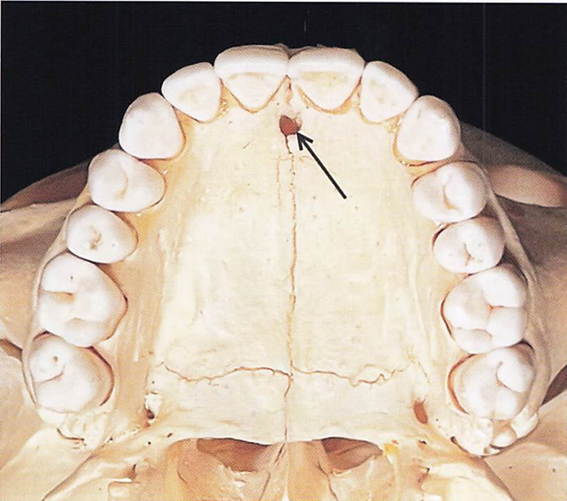

口蓋骨の写真を別に示す。 矢印で示す孔を通過する神経が分布するのはどれか。1つ選べ。

a.頬小帯

b.軟口蓋

c.口蓋扁桃

d.切歯乳頭

解答を見る

d